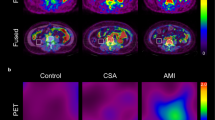

Patients were grouped into tertiles according to their TBR score in the LAD. The TBR scores ranged from 0.42 to 1.21 in the low tertile, 1.22 to 1.43 in the middle tertile and 1.44 to 2.42 in the high tertile. Figure 3 shows PFV, CPB, BMI, age and the prevalence of cardiovascular risk factors according to these TBR tertiles. Patients within the high TBR tertile had larger CPB, higher PFV, were older and had a higher prevalence of hypertension and coronary heart disease than did patients in the low TBR tertile (9.1 vs 3.5, p < 0.001 for CPB; 92.2 vs 71.5 mm3, p < 0.05 for PFV; 62.6 vs 57.2, p < 0.05 for age; 35.2 vs 16.7%, p < 0.05 for hypertension; and 20.4 vs 5.6%, p < 0.05 for coronary heart disease). Furthermore, patients within the high TBR tertile had a larger CPB and were older as compared to patients within the middle TBR tertile (9.1 vs 5.1; p = 0.001 for CPB and 62.6 vs 56.9, p < 0.05 for age). PET and CT images from representative patients within the low (Fig. 4) and high (Fig. 5) TBR tertiles are illustrated.

Cardiovascular risk factors and PET/CT variables according to TBRLAD tertiles. To enable a better graphic visualization CPB was multiplied by a factor of 10. The unpaired Student’s t test was used for statistical comparison. CHD coronary heart disease, FH family history of cardio- or cerebrovascular disease, PFV pericardial fat volume, CPB calcified plaque burden, BMI body mass index

PET/CT images of a 75-year-old female patient with no coronary risk factors. Coronal PET image shows no myocardial FDG uptake. Red circle indicates ROI. Axial CT images enable the exact anatomical localization of the left coronary artery. The SUVmax in the left coronary artery was 0.8, the mean venous SUV was 1.1 and the maximum TBRLAD was 0.74 (low tertile). PFV was 65.3 ml

PET/CT images of a 66-year-old male patient with coronary heart disease, a history of hypertension and smoking. Red circle indicates ROI. Coronal PET image shows no myocardial FDG uptake. Axial CT images allow identification of the anatomical location of the left coronary artery. The SUVmax in the left coronary artery was 1.6 and mean venous SUV was 1.1, resulting into a maximum TBRLAD of 1.45 (high tertile). The PFV was 175.9 ml